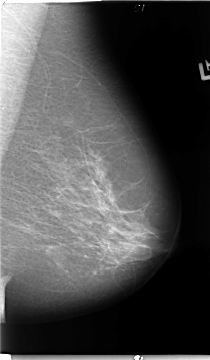

B_3098_1.LEFT_CC

LEFT_CC LINES 4672 PIXELS_PER_LINE 3056 BITS_PER_PIXEL 12 RESOLUTION 50 NON_OVERLAY